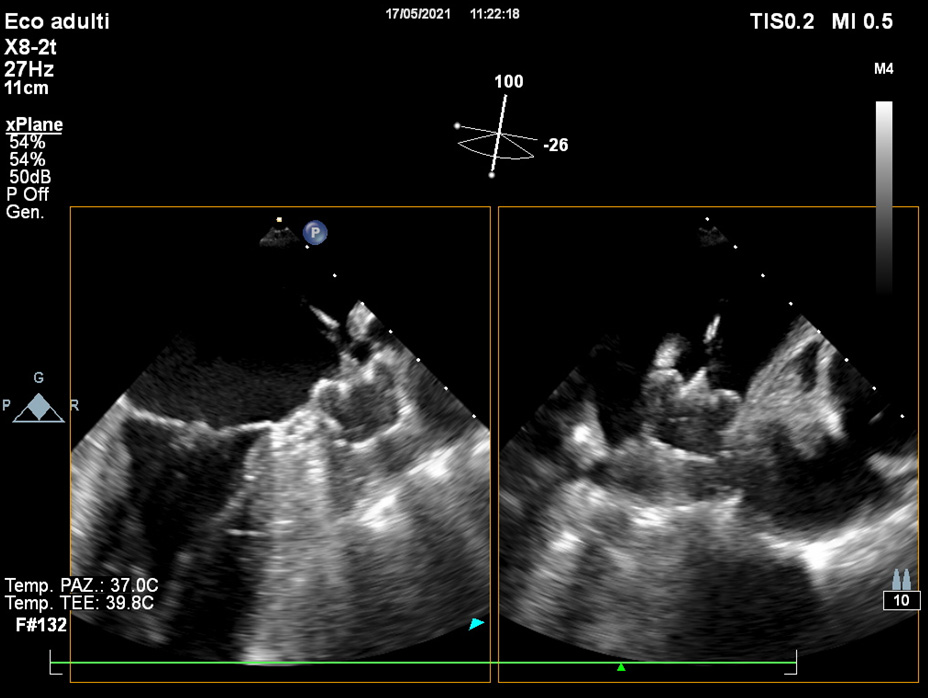

Once the presence of thrombus has been ruled out, TOE is used to assess LAA size and shape, number and location of LAA lobes [3, 36].

A full 0–135

Fig. 4.By use of multiplanar TOE, full 0–135